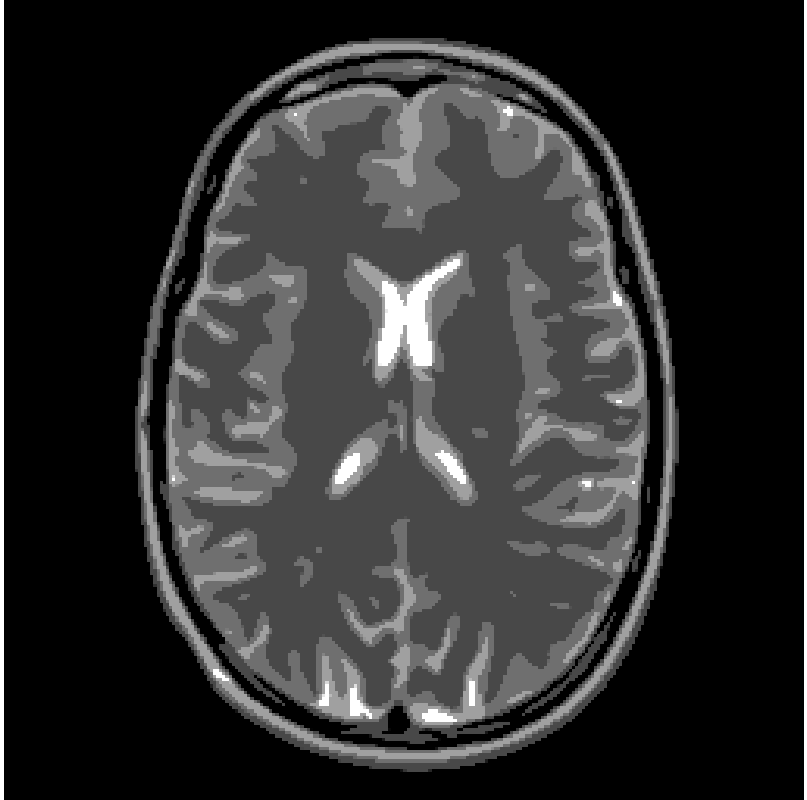

Concerning the real MRI data we compare IL and FNCR algorithms in the reconstructions of the brain image (T3 test), represented in figure 8. We report in table 6 the results obtained by reconstructing the noiseless data undersampled by , , masks.

From the table, we see that FNCR always outperforms IL.

In figure 10 we show the FCNR and IL reconstructions in case of mask and .

Finally in figure 9

we plot the reconstructed rows corresponding to the largest error (200-th row) for the true image and

the FNCR reconstruction (Figure 9(a)) and for the true image and

IL reconstruction (Figure 9(b)).

We observe that FNCR better fits the corresponding row of the original image.